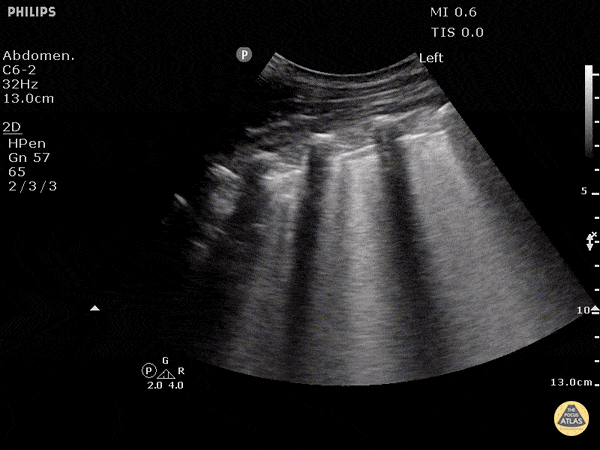

🌊 Épanchement pleural

Accumulation de liquide entre les plèvres – pariétale et viscérale.

Signes échographiques

- Espace anéchogène ou hypoéchogène entre la base pulmonaire et le diaphragme.

- Signe de la colonne vertébrale visible au-dessus du diaphragme grâce à la conduction du son par le liquide.

- Poumon collabé flottant dans le liquide (« signe de la méduse »).

Caractère du liquide

- Anechogène : transsudat simple.

- Complexe ou cloisonné : exsudat ou empyème.

- Échogène : hémothorax.